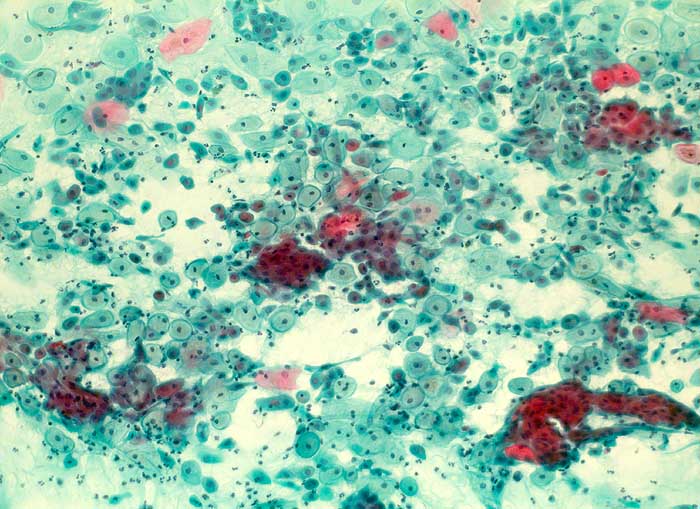

Postpartales Zellbild

Normalbefund

Zervix

Genitalorgane, weiblich

Zervixabstrich: metaplastische abgerundete Plattenepithelien, Parabasalzellen und Entzündungszellen.

Geburt vor 5 Wochen

Zytologie

100

33